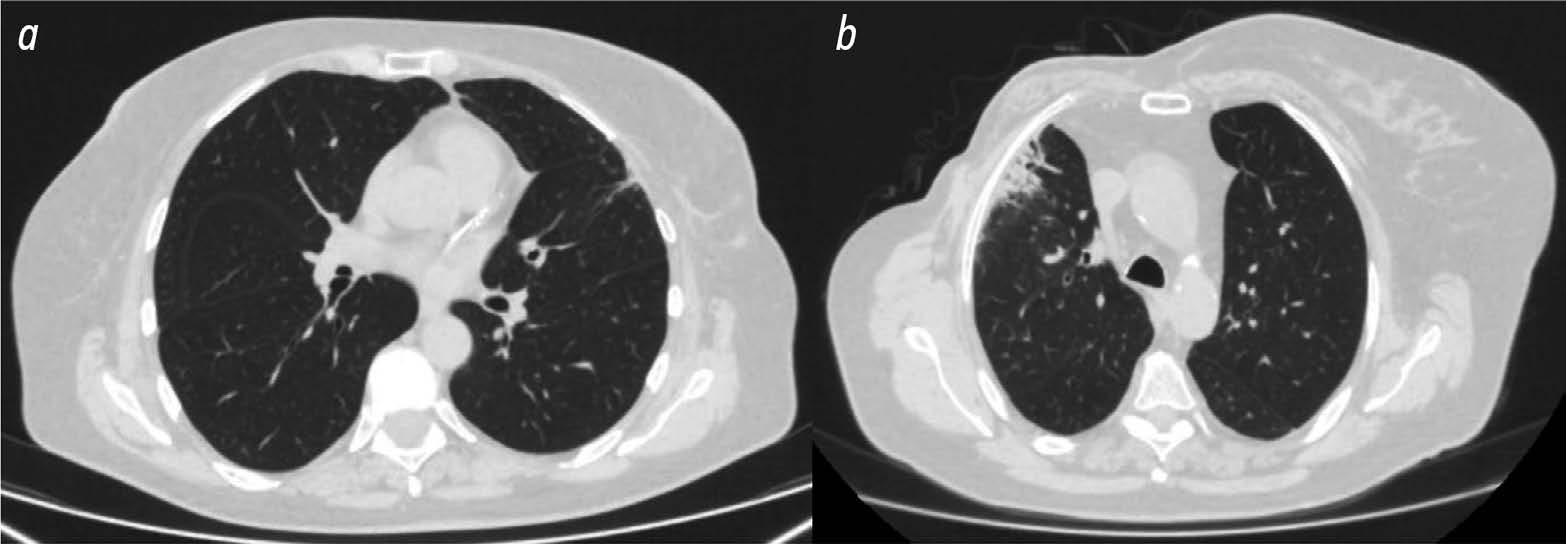

The role of computed tomography in the differential diagnosis of an intracardiac mass of the mitral valve: a case series

The differential diagnosis of an echocardiographically detected intracardiac mass in the mitral annulus can be challenging and usually requires a multimodal approach. This type of lesion is very often associated with subvalvular calcification of the mitral valve. The rare, caseous, variant is the most difficult to diagnose. This case series highlights the clinical significance of computed tomography in detecting and characterizing subvalvular mitral annular calcification when other modalities, particularly echocardiography, are inconclusive. The aim of this article was to raise awareness among specialists of the classic signs of caseous subvalvular calcification of the mitral annulus when visualized with different modalities. Special attention is also given to providing a differential diagnostic series that identifies features that differentiate subvalvular calcification of the mitral annulus from other conditions at this site. Healthcare professionals need to be aware of these mitral valve lesions in order to predict possible associated complications and plan a treatment strategy that may help avoid unnecessary surgical procedures in some cases.

893-901